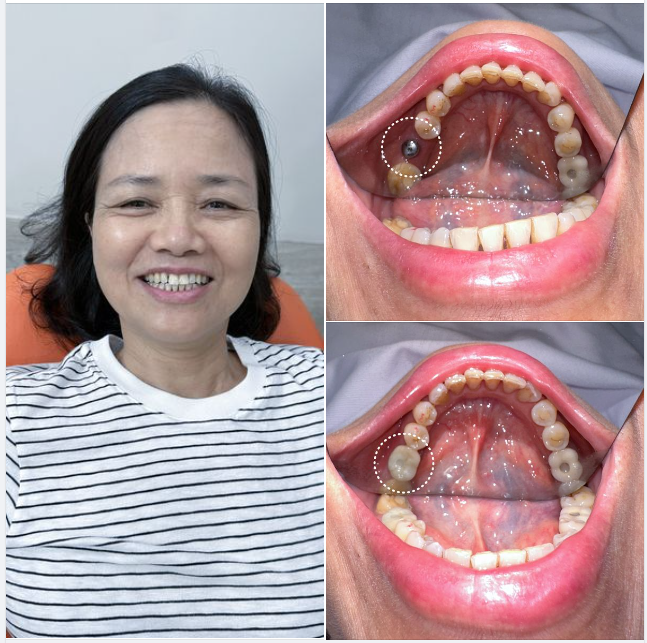

Trồng Răng Implant

Trồng Răng Implant -